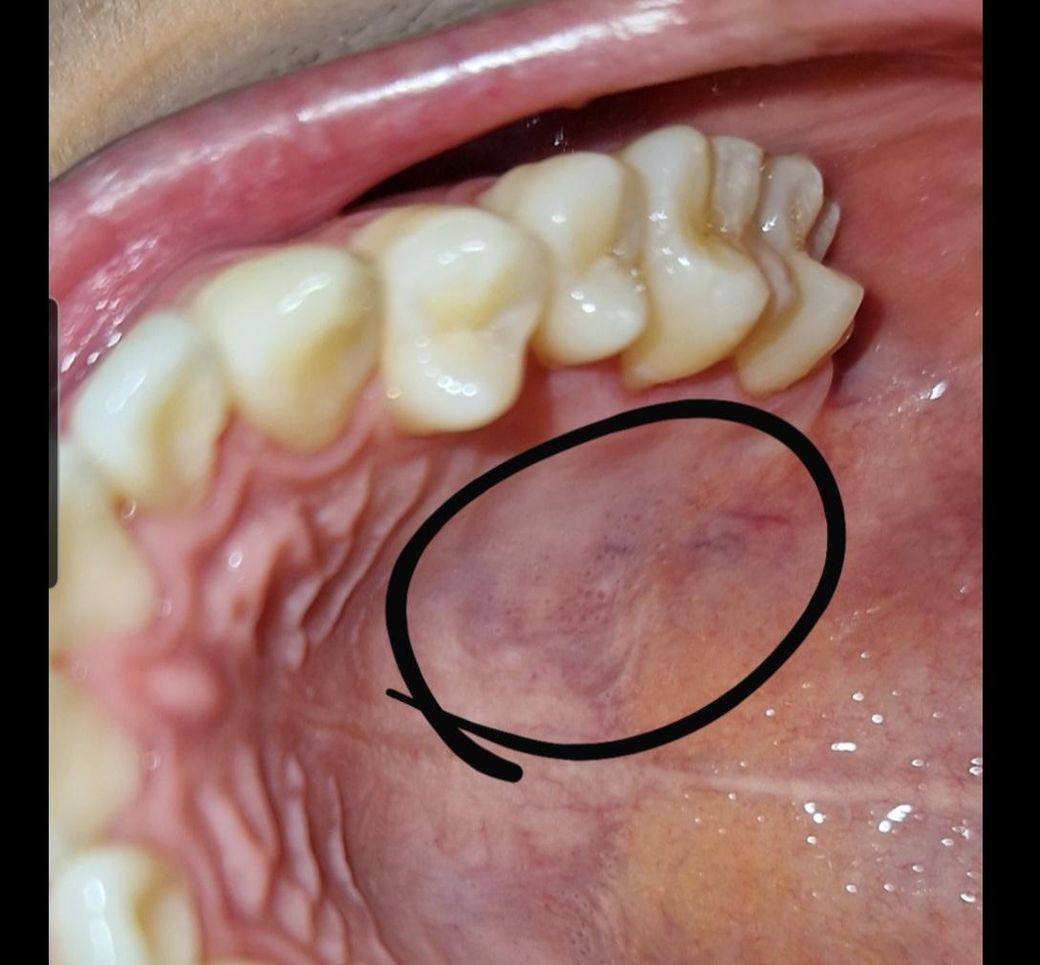

입 천장에 붉은색 점들같은게 있어요.

아프거나 하지는 않아요. 그냥 원래 있던걸까요?

암일수도 있나요? 병원에 가봐야하는지 궁금합니다

입천장이 자극을 받아서 생긴거니 크게 걱정은 안하셔도 될것같습니다. 암은 아니니 너무 걱정마세요.

연조직 질환, 바이러스나 세균 감염일 수 있고 아니면 단순히 입천장이 최근에 자극되어 그럴 수도 있습니다. 1~2주 내로 호전되지 않으면 치과를 가보시기 바랍니다.